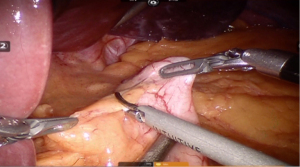

Using peri-gastric dissection, a small gastric pouch of capacity 20–30 mL is created. To start with, Phrenoesophageal membrane is divided using monopolar energy or ultrasonic shear while fundus of stomach is retracted caudally. Perigastric dissection is commenced by division of Gastrohepatic ligament between the first and second division of left gastric vessel and lesser sac is entered. It is done with the help of Harmonic scalpel in R1while stomach is being retracted laterally using R3. Care is taken to avoid injury to Vagus while entering lesser sac (Figures 5,6).

After delineating and entering lesser sac a 60-mm blue/tan cartridge is used by the surgeon on patient side to start division of stomach horizontally (Figures 7,8).